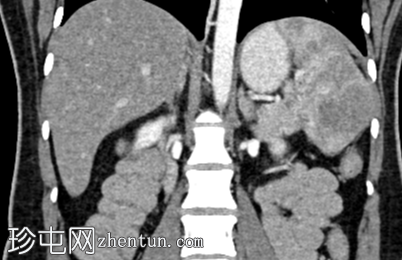

CT

冠状位增强扫描

动脉期

脾脏内可见一圆形低密度病灶,动脉期呈周边环状强化,延迟期呈轻微向心性充盈

未见钙化、动静脉畸形或动脉瘤

脾脏硬化性血管瘤样结节性变是一种良

性病

变,常在中年女性中偶然发现。

影像

学特征为:病灶周围呈放射状强化,中心呈放射状强化,周围环状强化,中心充盈轻微。增强扫描后可见中央星状瘢痕。